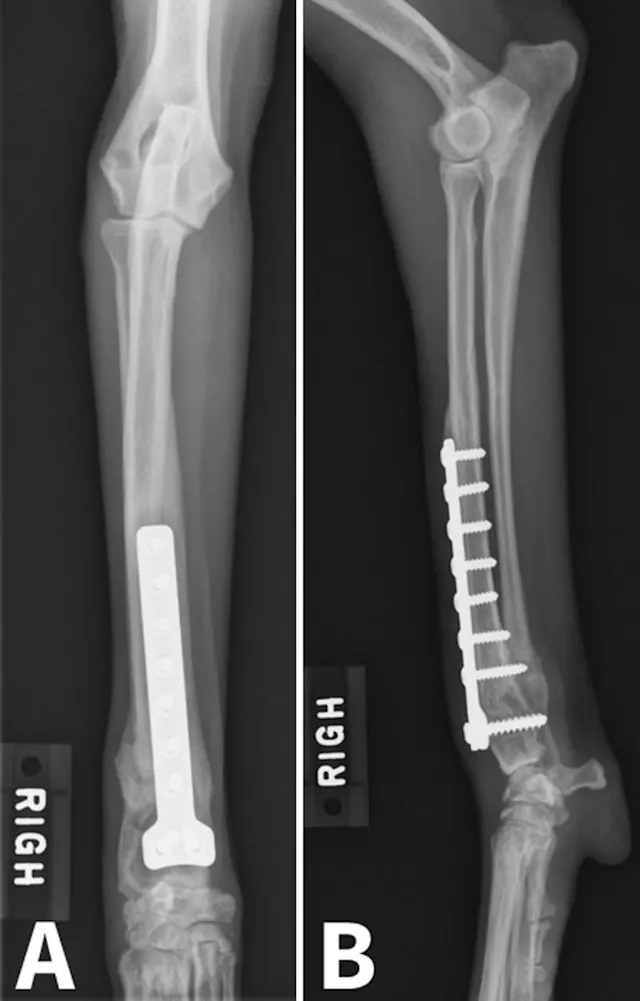

Figure 1. Radial valgus and external torsion.

Physeal trauma is a common cause of ALD, particularly when paired bones are involved. Distal forelimb trauma in immature patients can cause a compression injury (Salter V fracture)2 to the conical-shaped distal ulnar physis, leading to premature closure of the distal ulnar physis. This results in cessation of ulnar growth. Although the radius will continue to grow in affected patients, valgus deviation, cranial bowing of the radius, and torsional deformity can typically develop as a result of the constraining effect of the ulna.3

Image courtesy of Derek B. Fox, DVM, PhD, DACVS, University of Missouri